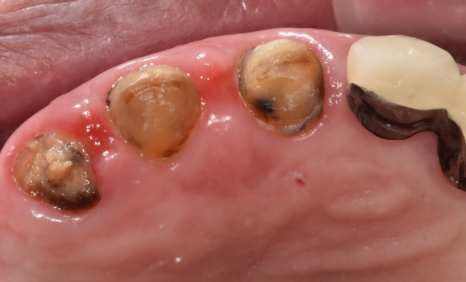

먼저, 문제의 시작이 된

오른쪽 아래 임플란트 보철을 제거했습니다.

너무 낮게 만들어진 보철을 빼고,

다른 치아들과 조화를 이루도록

좀 더 높이를 살려 다시 제작하기로 했습니다.

다음으로,

많이 닳은 아래 앞니 7개를 살려보기로 했습니다.

230211

다행히 이 아래 앞니들은 흔들림이 크지 않아

뿌리가 버텨주는 상태였기 때문에,

신경치료를 먼저 진행한 뒤

크라운으로 씌워 높이를 다시 세워 주었습니다.